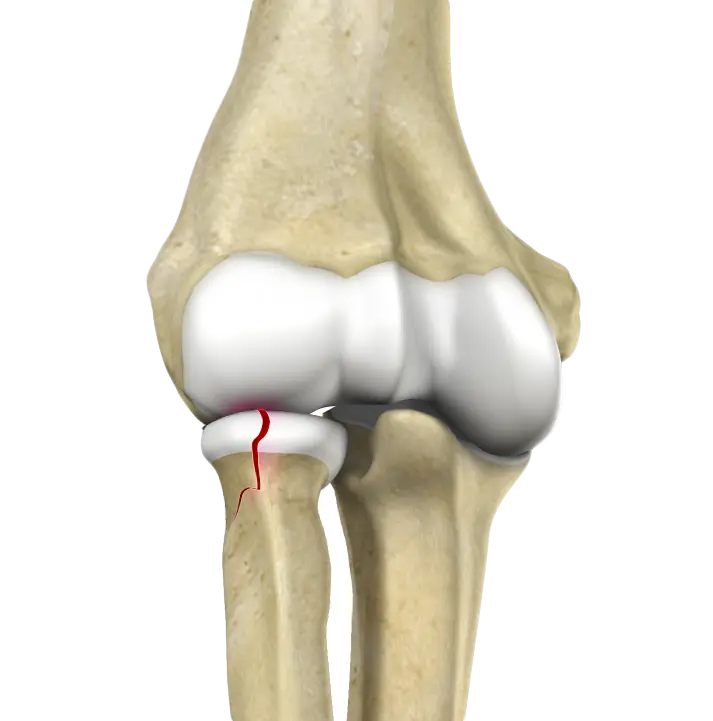

Radial Head Fractures of the Elbow

Radial head fractures are very common and occur in almost 20% of acute elbow injuries.